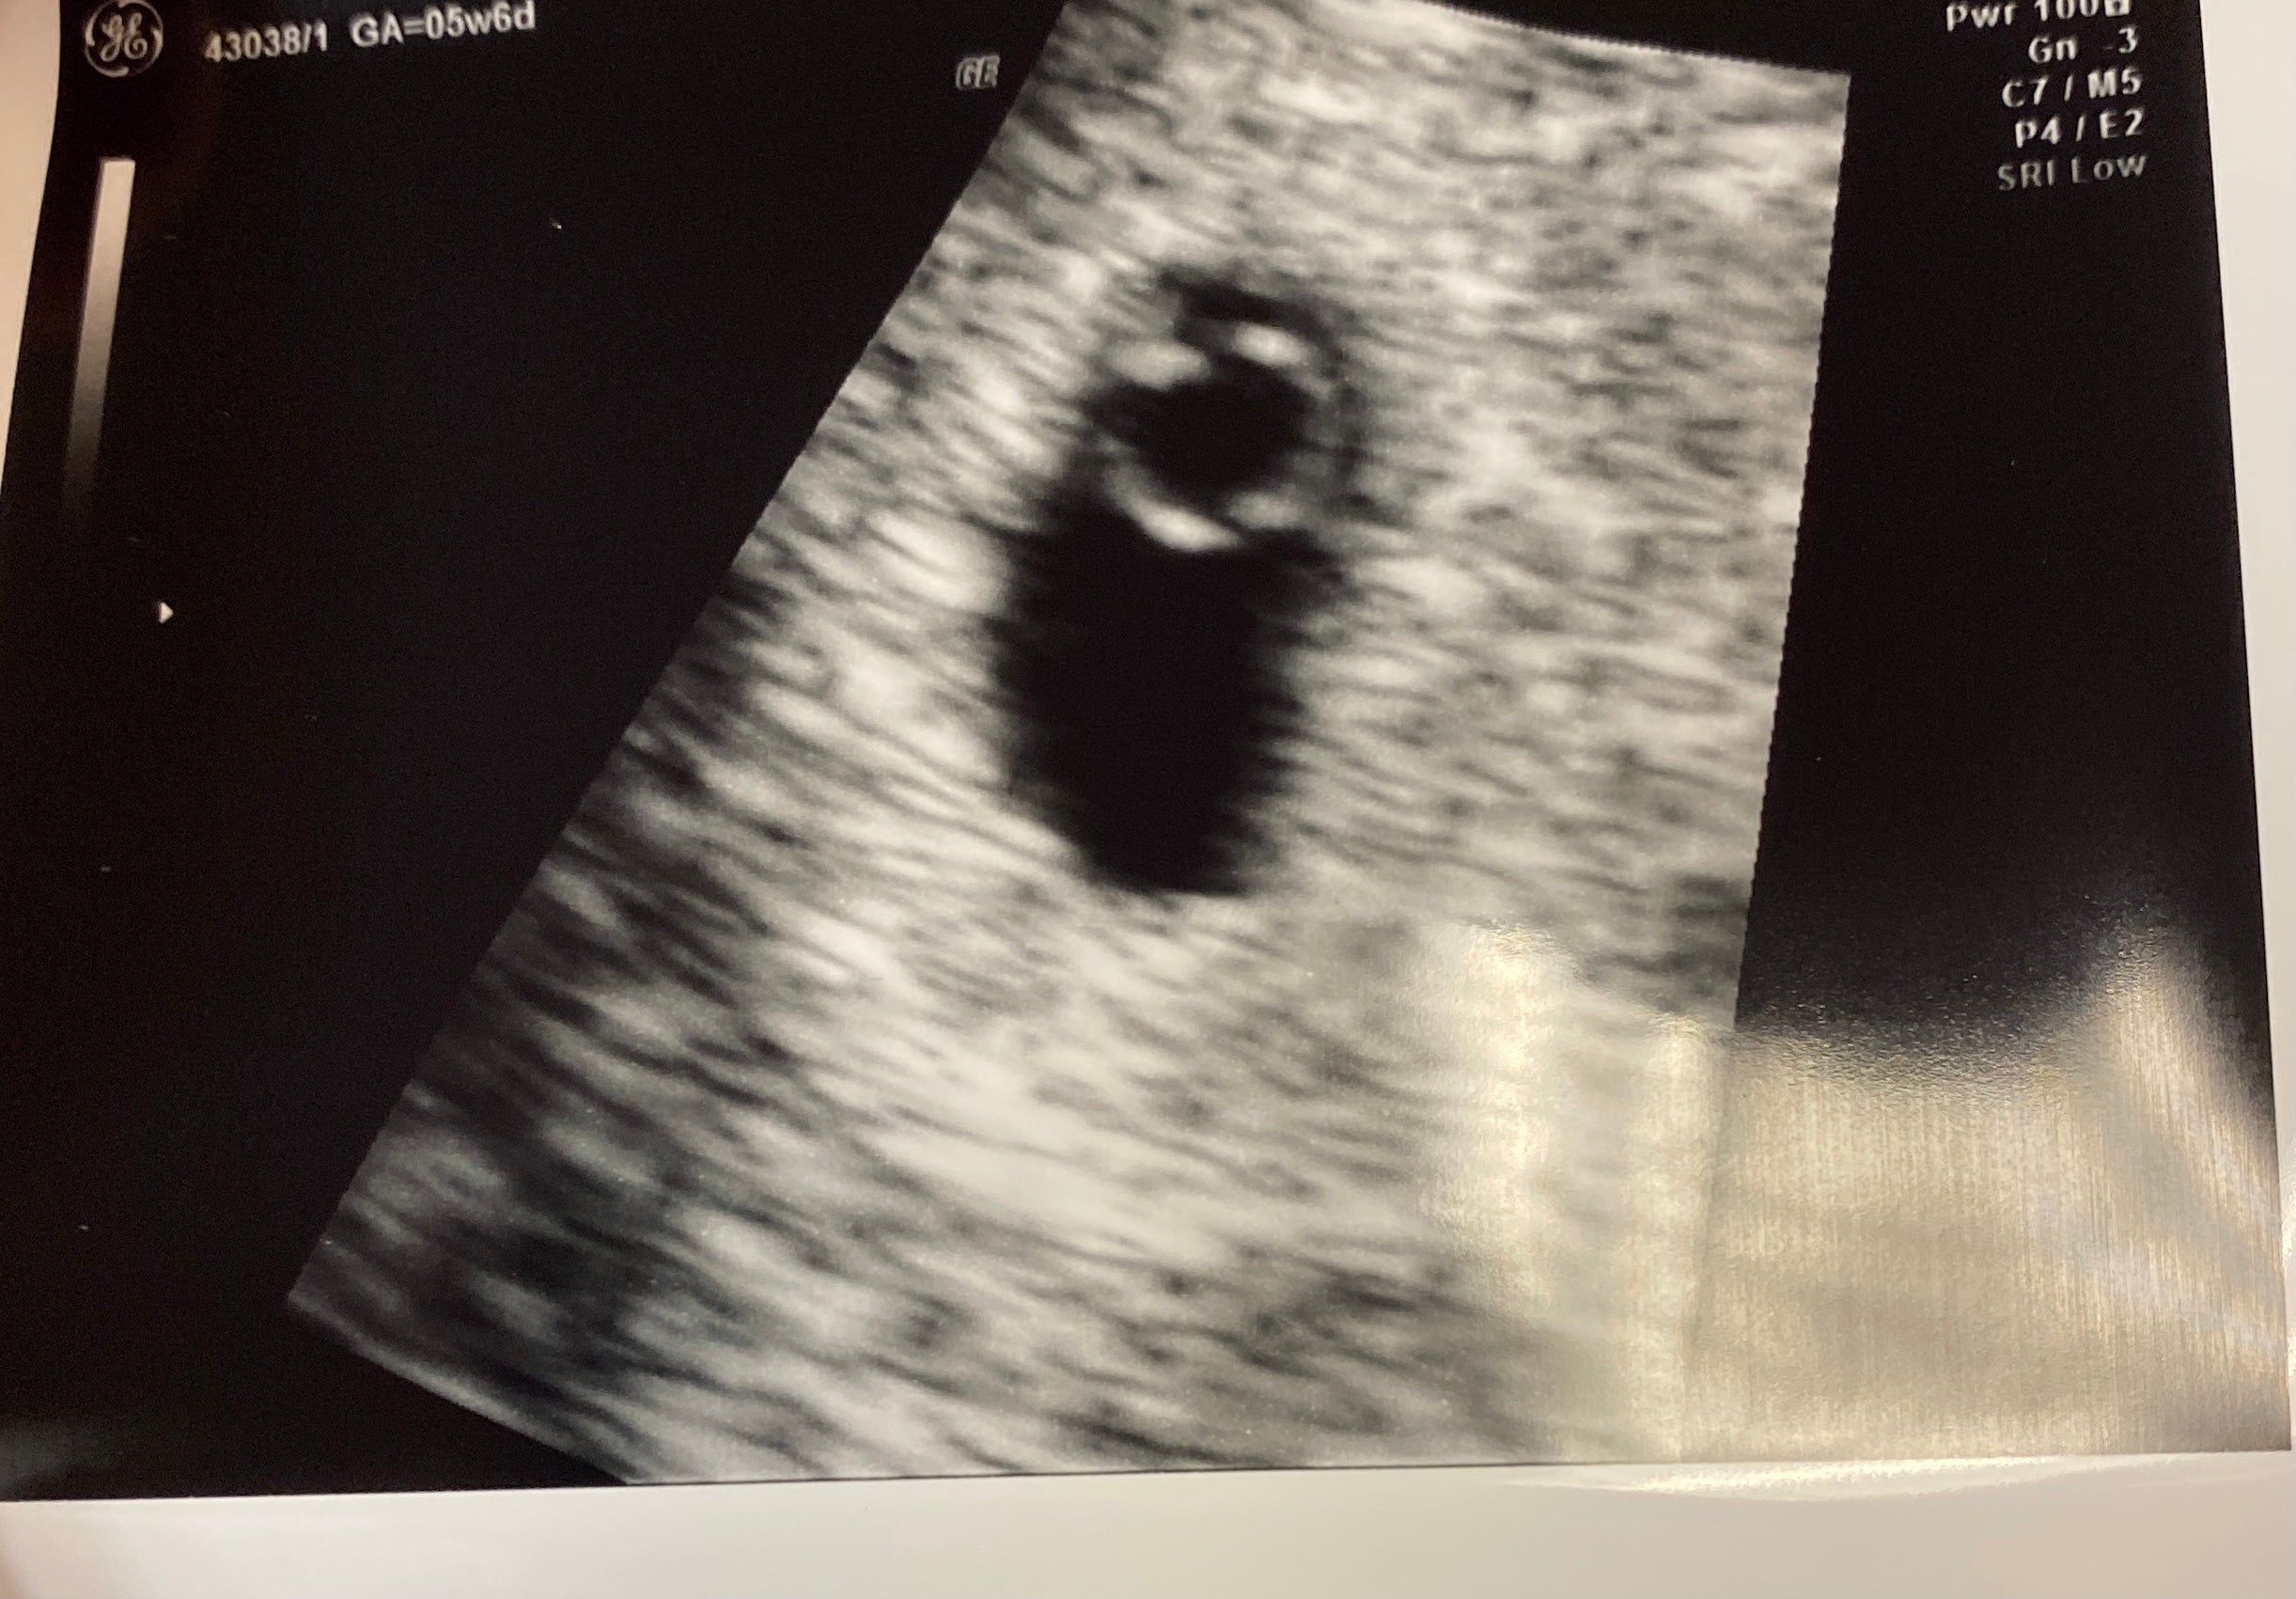

I’ve been wanting to get pregnant for years now but didn’t have the support I needed, and I was told with my PCOS it would probably be difficult to get pregnant, so I never even attempted. I broke up with my boyfriend of 8 years and got with my now fiancè, and she was on board for kids as soon as I was willing to try. So we bought the Mosie Baby Kit in the beginning of August, used an app to figure out my ovulation day, which was August 28, her brother donated sperm, we inseminated 3 times the week of my ovulation, and I got pregnant on my first try. And we are due to have a baby in May!